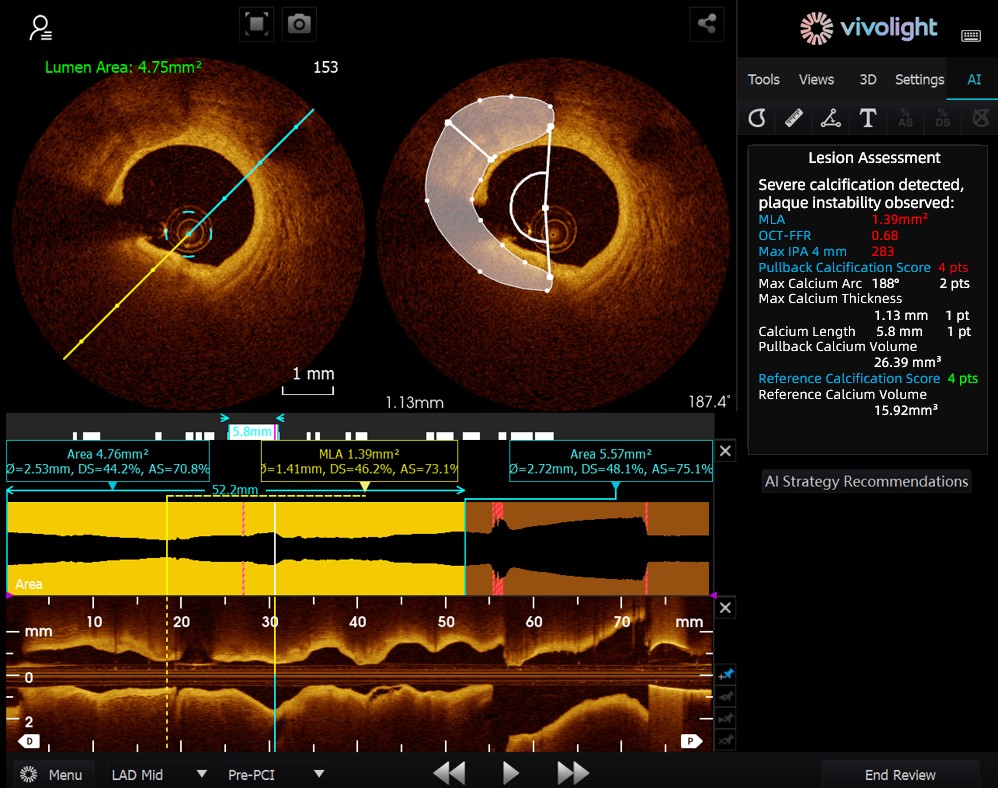

Desarrollado a partir del sistema OCT de Vivolight Medical, el AI-OCT es un sistema inteligente de apoyo a la decisión de última generación para imágenes intravasculares. Integra datos diagnósticos de imágenes intravasculares dispersos —como el diámetro luminal, las lesiones causantes, la OCT-FFR y las características de la placa— en estrategias de tratamiento integrales y recomendaciones prácticas. Como software de investigación independiente integrado en la plataforma OCT, se desarrolla en colaboración con diversos hospitales para crear versiones personalizadas que se adapten a necesidades clínicas específicas.

Durante el foro de vanguardia, los expertos destacaron que el sistema AI-OCT representa un cambio transformador, pasando de la mera visualización de imágenes a la elaboración de planes de tratamiento, lo que permite abordar los desafíos de la sobrecarga de información y la compleja toma de decisiones en los procedimientos de intervención cardíaca, que tradicionalmente dependen en gran medida de la experiencia del médico. Entre las principales ventajas del sistema se incluyen:

●Guía intraoperatoria en tiempo real: Organiza de forma dinámica la información diagnóstica durante la cirugía, proporcionando métricas clave y recomendaciones clínicas.

●Toma de decisiones basada en la evidencia: Todas las sugerencias se ajustan al consenso de expertos y a las guías clínicas, lo que garantiza rigor y fiabilidad.

El sistema AI-OCT adopta una arquitectura de "modelo pequeño + macrodatos + modelo grande": los modelos pequeños permiten una interpretación precisa de las imágenes, mientras que los modelos grandes impulsan un razonamiento clínico integral. Gracias a bases de datos cardiovasculares de alta calidad y a la tecnología de Generación Aumentada por Recuperación (RAG), ofrece soporte integral, desde la evaluación de lesiones hasta el desarrollo de estrategias de tratamiento.